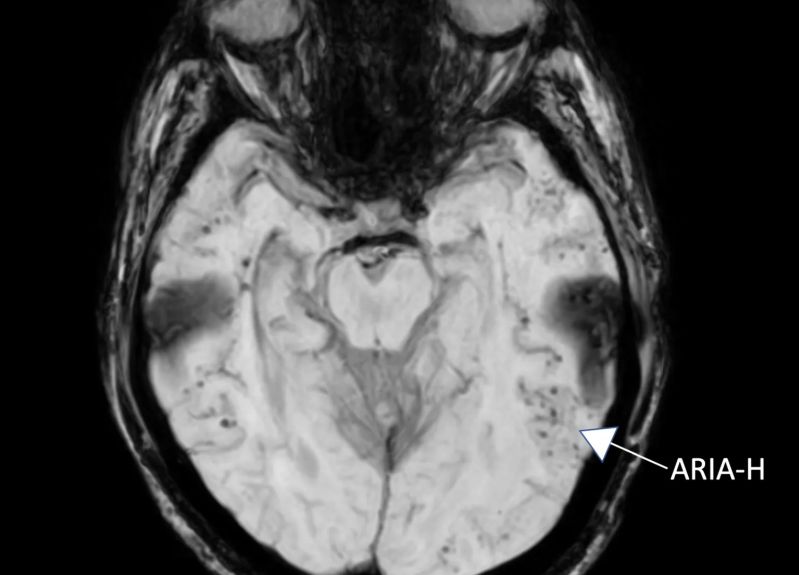

Risonanza magnetica a suscettibilità ponderata durante il mio episodio di ARIA del 2017, che mostra microemorragie bilaterali multiple nei lobi temporali. Le microemorragie (ARIA-H) appaiono come punti neri, per lo più raggruppati attorno ai vasi sanguigni. Sono strettamente correlati se non identici alle microemorragie associate all'angiopatia amiloide cerebrale. Fonte: Dan Gibbs

Attualmente il test migliore è un protocollo MRI chiamato 'scansione a suscettibilità ponderata' (SWI, susceptibility weighted imaging), una sequenza particolarmente sensibile al sangue e ad altri composti contenenti ferro che distorcono il campo magnetico locale. Sebbene la SWI-MRI non sia interamente specifica per il sangue, la distribuzione di questi punti neri attorno ai vasi sanguigni si correla molto bene con la presenza all'autopsia delle microemorragie associate alla CAA.

Le persone che hanno avuto ARIA-H (anomalie di scansione correlate all'amiloide, di tipo microemorragia) durante il trattamento con un anticorpo monoclonale anti-amiloide possono avere CAA e dovrebbero essere attentamente monitorate con MRI se il farmaco continua. Dovrebbe anche essere usata cautela nell'uso di anticoagulanti come il warfarin o l'attivatore tessutale del plasminogeno (t-PA) poiché possono aumentare la possibilità di un'emorragia potenzialmente fatale in chi ha CAA.